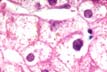

Fig 40 - LIPOFUSCIN

D-PAS

+ acid fast

+ autofluorescent.

Intralysosomal.

Increases in brown atrophy.